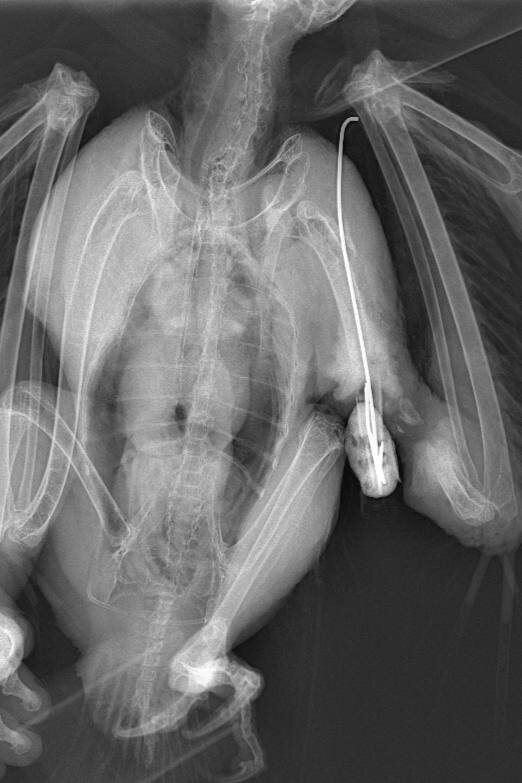

После остеосинтеза — операции по фиксации костей при переломах — строгое соблюдение рекомендаций врача критически важно. Вот почему: 🦴 1. Нагрузки = угроза срыва фиксации Даже если животное чувствует себя лучше — это не значит, что кость срослась. Преждевременные нагрузки могут привести к: смещению импланта; повторному перелому; необходимости повторной операции. ⏳ 2. Костная ткань срастается не мгновенно На полное восстановление после остеосинтеза нужно в среднем 6–8 недель, иногда больше. Нарушение режима в этот период может замедлить или полностью остановить заживление. 🐾 3. Ограничение подвижности — не жестокость, а забота Да, ограничение активности (вплоть до клеточного содержания) может вызывать стресс у владельца и питомца. Но это — единственный способ дать организму шанс на полноценное восстановление. ⚠️ 4. Игнорирование рекомендаций = риск осложнений Возможные последствия: - воспаление в области фиксации; - образование ложного сустава; - повторная операция и длительная ре